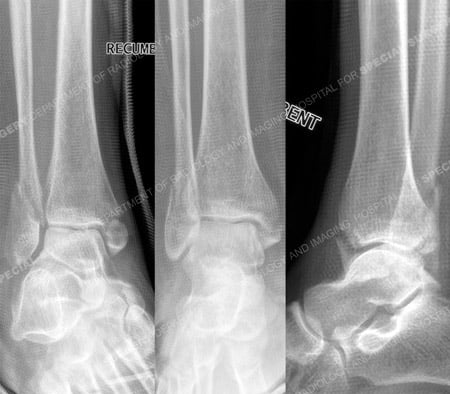

A 50-year-old female fell approximately 3 feet from a step ladder. She presented to the HSS Orthopedic Trauma Service with a bimalleolar ankle fracture placed in a cast by the referring hospital. Open Reduction and Internal Fixation (ORIF) was performed by Dr. David L. Helfet with placement of a plate and multiple screws, including an interfragmentary lag screw, for the fibula fracture and 2 screws for fixation of the medial malleolus fracture. She returned at regular follow-up intervals and healed uneventfully and at 8 months following surgery radiographs illustrated a healed ankle fracture and clinically she reported no pain and a full return to pre-injury activities.

Radiographs reveal a displaced bimalleolar ankle fracture.